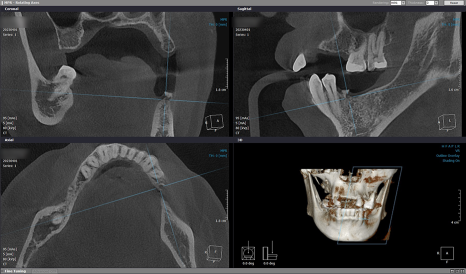

그리고 환자분의

우측 임플란트 수술을 진행했습니다.

이 부위는 모두 2차 수술까지 필요한 경우로,

임플란트 픽스처 고정 후

커버스크류를 씌우고 잇몸을 봉합한 뒤

다음 내원 때 뵙기로 했습니다.

4개월의 골 유착 기간을 갖고

내원해 주신 환자분의

#14번 치아는 본을 뜨고 보철물 수복을 해드렸으며

2차 수술을 진행한 #16, #17, #46, #47번은

잇몸을 열고 커버 스크류 제거 후

힐링 어버트먼트를 체결해 드렸답니다.